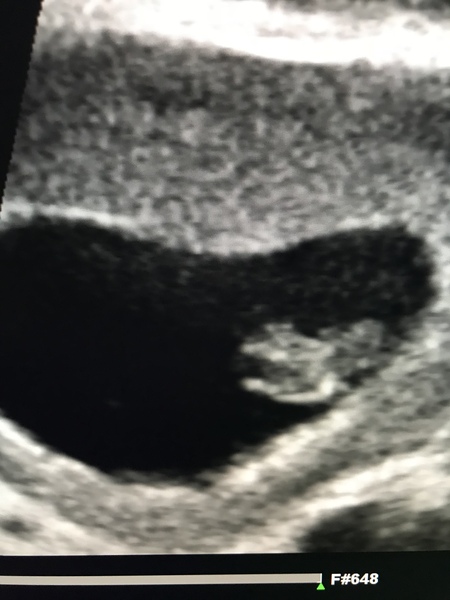

Had an early private scan today so it’s all starting to feel so real! Seeing our little bean and flickering heartbeat 💗 has made up for how sick I am currently feeling 🤢😍

Had my dating scan today and things looked good! It was pretty surreal to see the little bean in there with a nice strong heartbeat flickering away! As you said @Upsydasiy it does help make the nausea feel worth it! Sonographer was lovely and let DH come in for a bit and look too.

They’ve bumped up my due date to 2nd Jan from the 4th but said the measurement did were bang on for my dates so I’m not sure how that works!

@emdoc Yay! I'm pleased your scan went well! Its a good picture for this early on too.